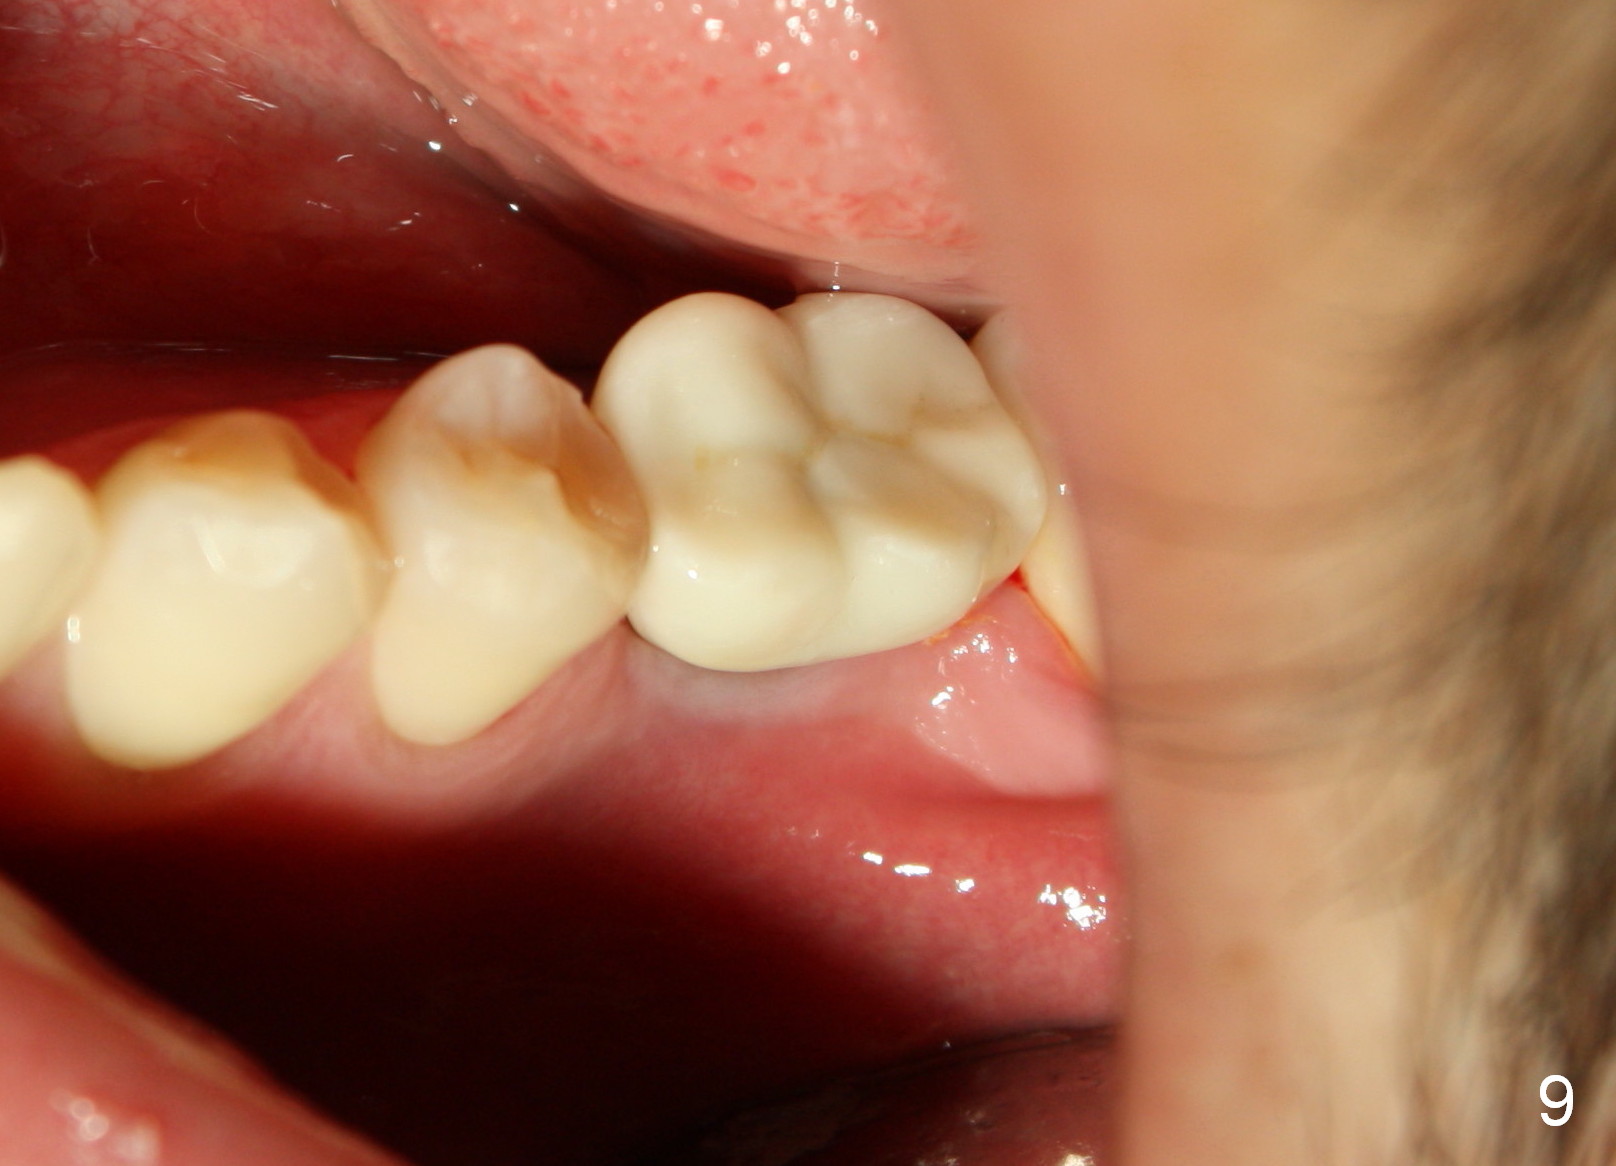

A 22-year-old man requested extraction of the tooth #19 (Fig.1).  X-ray was taken 3 and 8 months post extraction, respectively (Fig.2,3).  A 6x17 mm Tatum tapered implant was placed (Fig.4,5). A 5 mm (in diameter) 0 degree unipost (5 mm in height) was prepared 7 months after implant placement. Due to limited space, time was spent for extraoral and intraoral reduction of the abutment.

Fig.6 shows Emax crown with limited space for porcelain before cementation.  In fact, the crown was fractured during cementation at the area indicated by arrowhead in Fig.6.  A new crown was fabricated with core material used in the occlusal portion without porcelain overlay.  The new crown was then cemented without complication.